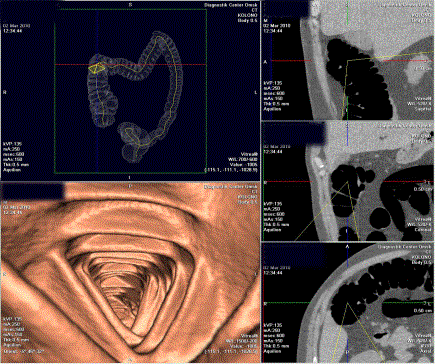

Рисунок 2.

Виртуальная колоноскопия. Качественная подготовка толстой кишки.